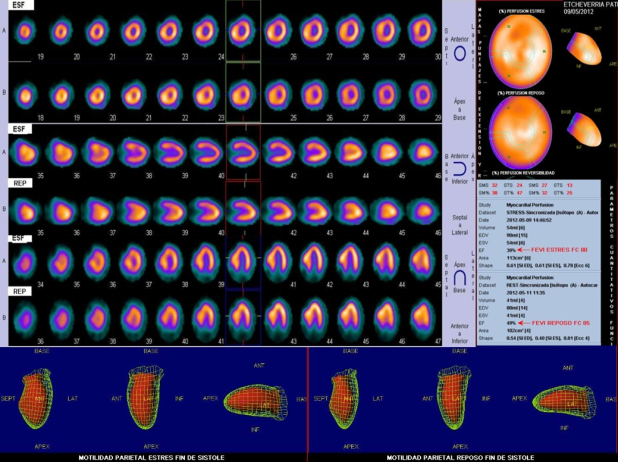

Los hallazgos del SPM son ilustrados en la fig. 4; se observa HVI severa a predominio septal, dilatación transitoria del ventrículo izquierdo (VI), fracción de eyección ventricular izquierda (FEVI) basal en el límite normal inferior (49%), con caída significativa post-esfuerzo (39%). Sin embargo, no existen defectos de perfusión de tipo segmentario.

Si bien el SPM no representa el estudio de elección en pacientes con sospecha de MCH, en nuestro caso el mismo fue de orientación diagnóstica al demostrar HVI severa a predominio septal y trastornos funcionales acompañantes. En particular, la dilatación transitoria del VI sin defectos de perfusión se ha reportado en pacientes con MCH y coronarias epicárdicas normales(11), siendo controversial si se trata de una verdadera dilatación post-isquémica o si la misma es aparente por isquemia subendocárdica difusa. De todas maneras, parece razonable considerar que existe una alteración de la reserva coronaria en estos pacientes, y que la misma se traduce como una verdadera isquemia durante el ejercicio que incluso puede explicar la caída de la FEVI. También puede interpretarse que una obstrucción dinámica severa es capaz de producir una caída de la FEVI que aumente la desproporción ya conocida entre número de vasos y masa miocárdica que tienen estos pacientes.